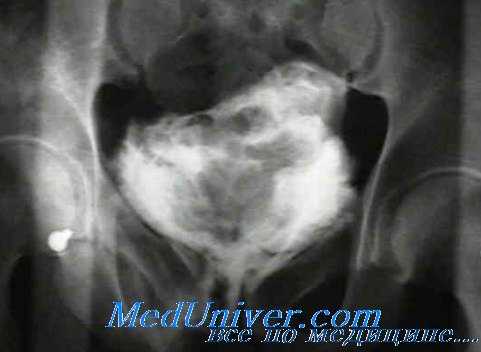

Контрастное исследование при травме прямой кишки

• Рентгенография органов брюшной полости/таза: признаки свободного газа в брюшной полости? Задержавшееся инородное тело? Сопутствующие повреждения скелета?

• КТ (если возможно, с тройным контрастированием водорастворимым препаратом, т.е. перорально, внутривенно и перректально): протяженность повреждения, перфорация и т.д.

• Рентгенография: признаки свободного газа в брюшной полости? Вовлечение других органов и систем (например, травматическая диафрагмальная грыжа, повреждения грудной клетки, средостения, забрюшинного пространства), задержавшиеся инородные тела? Сопутствующие повреждения скелета?